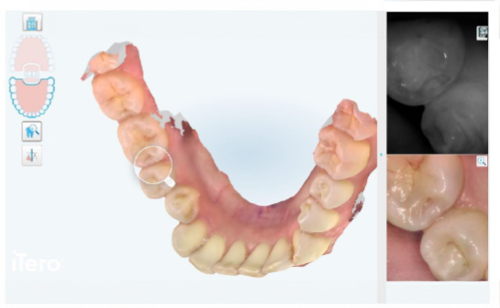

現在のお口の状態を写真で記録し治療後と比較したり、治療説明で利用します。

口腔内をスキャンする機械を用いて、歯の本数、虫歯の有無、詰め物の状態を3次元的に検査・記録します。

その後、歯科医師により直接確認を行います。

口腔内スキャンを用いて、虫歯のチェックや歯の汚れを染め出してチェックします。

虫歯の精密検査を行う際は染め出しをせず口腔内スキャンを行う場合もあります。